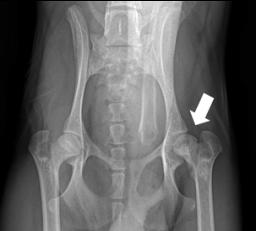

При рентгенологическом обследовании (рис. 6) у

96 собак (39 %) выявлены признаки артрита (расширение суставной щели,

разрежение костной ткани, изменение рельефа суставных поверхностей, уплотнение

тканей суставных связок).

Рис. 6. Рентгенологический снимок тазо-бедренного сустава

двухгодовалой немецкой овчарки с

признаками артрита.